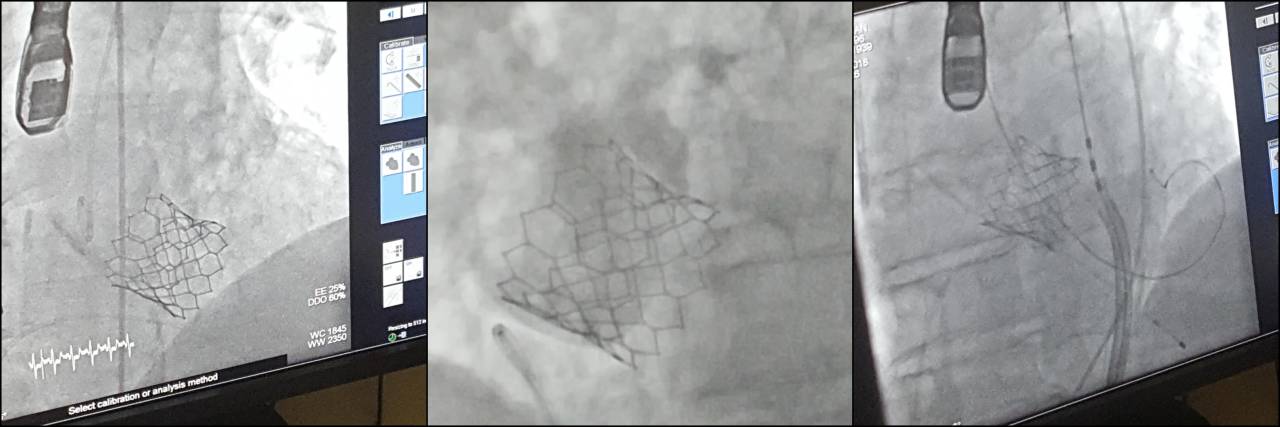

V torek so v UKC Maribor, v katetrskem laboratoriju Oddelka za kardiologijo in angiologijo, uspešno izvedli prvo nekirurško vstavitev aortne zaklopke.

S tem, z uvedbo tovrstne metode, se v Univerzitetnem kliničnem centru Maribor povečuje dostopnost in obenem omogoča enaka kvaliteta zdravljenja pri bolnikih z okvaro aortne zaklopke tudi v severovzhodni Sloveniji.